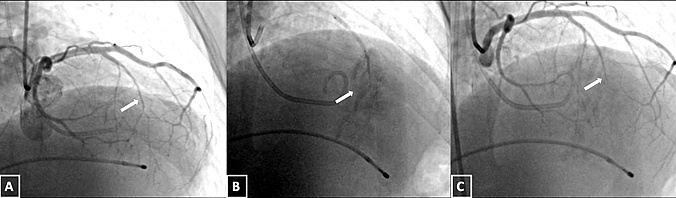

The procedure was performed under conscious sedation and local anesthesia. As mentioned in our previous study,11 femoral artery access was achieved using two 6-French sheaths—one for the guiding catheter to deliver the ablative agent and another for continuous monitoring of the midventricular gradient throughout the procedure. Femoral venous access was also obtained to place a temporary pacemaker in the right ventricular apex, ensuring readiness to manage potential advanced atrioventricular (AV) blocks during the procedure. A pigtail catheter was positioned in the left ventricle to establish baseline midventricular pressure gradients. Following this, the Brockenbrough-Braunwald-Morrow sign was evaluated, characterized by a post-extrasystolic increase in gradient, confirming dynamic obstruction at the midventricular level13 (Figure 4A).

Coronary angiography was performed to identify an appropriate septal branch supplying the midventricular myocardium, typically visualized in right anterior oblique projections (Figure 5A). A 0.014-inch guidewire was advanced into the chosen septal artery, and an over-the-wire balloon catheter was positioned to ensure vessel occlusion without contrast leakage. A contrast agent was initially injected selectively under fluoroscopy to confirm the target vessel, observe the absence of contrast leakage, and verify its supply to the hypertrophied myocardium. Once the target vessel was confirmed, polidocanol was injected into the balloon-occluded artery to achieve controlled ablation (Figure 5B). The final angiographic image confirmed the successful occlusion of the septal artery while preserving normal blood flow in the left anterior descending artery (Figure 5C). TTE revealed septal brightening at the target site during this process, confirming accurate delivery to the intended region (Figure 6). Polidocanol was infused through the balloon catheter in incremental doses, with its foam-like structure enabling focused ablation across the hypertrophied midventricular myocardium. Doses ranged from 2 to 7 mL depending on vessel size, hemodynamic responses, and real-time electrocardiographic changes, such as QRS widening. The procedure was deemed successful if a reduction of 50% or more in the midventricular pressure gradient was achieved immediately post-ablation, as verified by hemodynamic and echocardiographic measurements. Additionally, the resolution of the Brockenbrough-Braunwald-Morrow sign (Figure 4B), which served as an important marker to guide the effectiveness of the ablation procedure, along with the absence of significant complications, such as high-degree AV block or sustained ventricular arrhythmias, were key indicators of procedural success and safety.